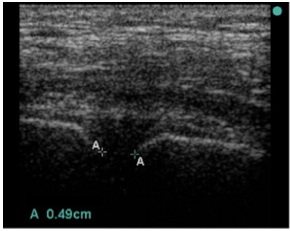

There is one other trick which can give you a really valuable clue. Symphyseal diastasis is the hall mark of the AP compression injury. This is the sign that the “book is open”. If you can identify this then you can identify the group that is likely to benefit from a binder to “close the book” (although some will have vertical shear so care is still required). This is yet another use for my trusty companion, the handheld ultrasound.

The width of the pubic symphysis can easily be measured with the same high frequency linear probe that you use to exclude a pneumothorax. The upper limit of normal width measured at the point shown in the image is <25mm in adults (Bauman). I am not aware of any published data on children. As with all things there is a bit of variation here and cadaver studies have shown that anterior sacroiliac ligament disruption is likely for displacement greater than 45 mm and unlikely for values less than 18mm. So if the symphysis is less than 18mm you can be very confident the pelvis is not “open”.

Note that in the source study for the reference range they failed to achieve a measurement in one case because the symphysis was wider than the width of their probe. You may have to move the probe from side to side to pick up both sides of a really wide symphysis.